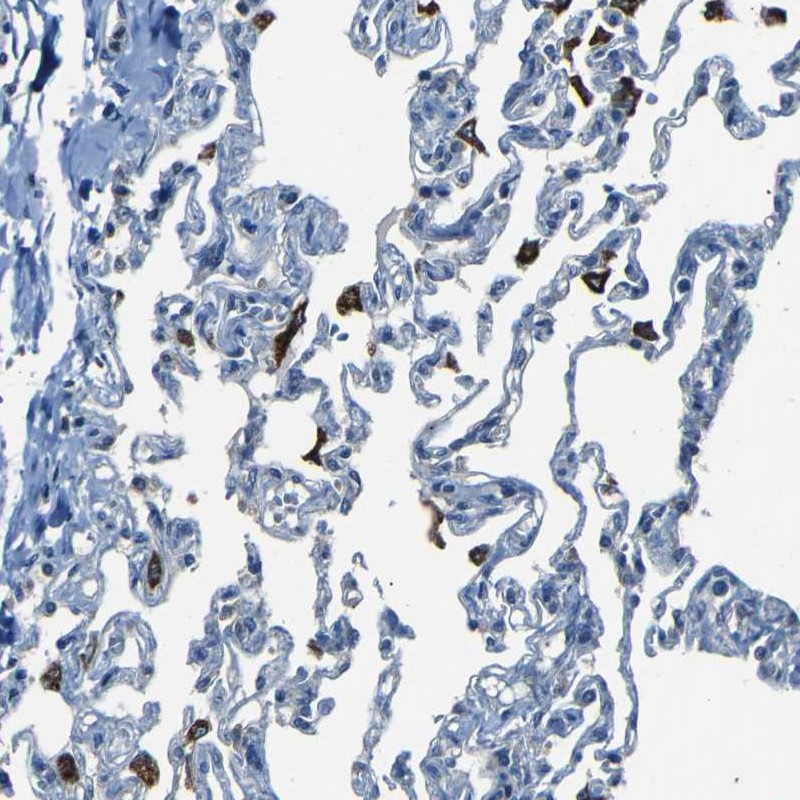

Immunohistochemical staining of human lung shows strong cytoplasmic positivity in macrophages.